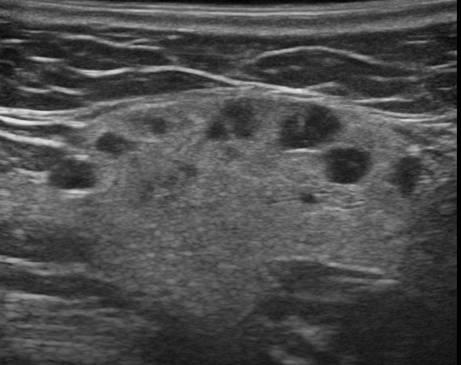

Hạch tuyến nước bọt

» Thông tin: Nữ giới – 66 tuổi.

» Lâm sàng: Sưng đau vùng góc hàm.

# Hạch lành tính ngoại vi tuyến nước bọt dưới hàm.